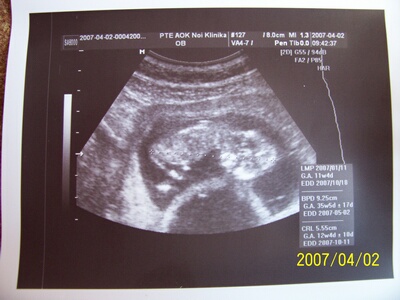

Voltam 12 hetes uh-on, szuper volt, tarkóradő normális: A baba: 2mm, B baba: 1 mm.

Méret: A baba: 55,5 mm, B baba: 54,5 mm

Két magzatburok, két lepény!

Uh. alapján számitott kor 12+4